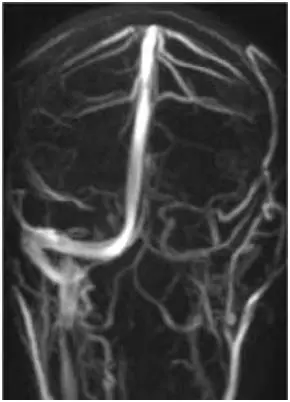

Le Vene Intra- ed Extracraniche in Relazione con l’Emicrania Cronica: Modificazioni Elettroencefalografiche Indotte dalla Venoplastica con Palloncino

Nei pazienti con emicrania cronica e insufficienza venosa cerebrospinale, la venoplastica con palloncino ha migliorato il flusso giugulare e normalizzato il ritmo alfa cerebrale, con riduzione significativa del dolore e possibile correlazione tra circolazione venosa e attività cerebrale.